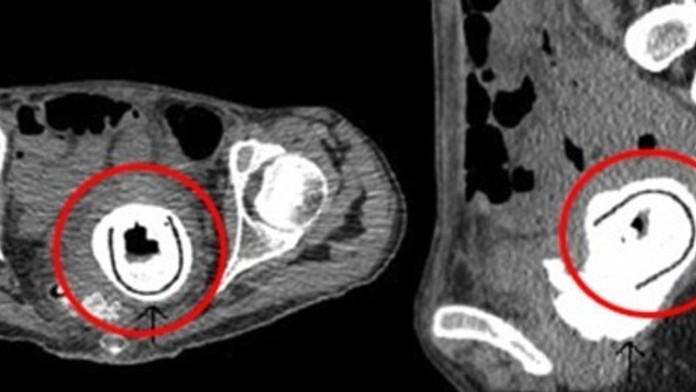

Chirurgovia našli takmer 13-centimetrovú sexuálnu hračku v ženskej pošve. Mala ju tam celých 10 rokov.

Netušila však, čo jej mohlo spôsobiť takéto ťažkosti. Lekári ju po potrebných vyšetreniach poslali na röntgen. To, čo tam videli, ich zarazilo. Žena mala celých desať rokov v maternici sexuálnu hračku. Priznala, že si nepamätá, ako sa tam hračka dostala. Je však podľa nej možné, že ju používala pod vplyvom alkoholu.

Hračka jej ohrozovala život. Mohla spôsobiť vnútorné poranenia, ktoré by mali vážne následky. Jeden čas žena trpela odtokom moču do pošvy a mala obštrukčnú uropatiu.